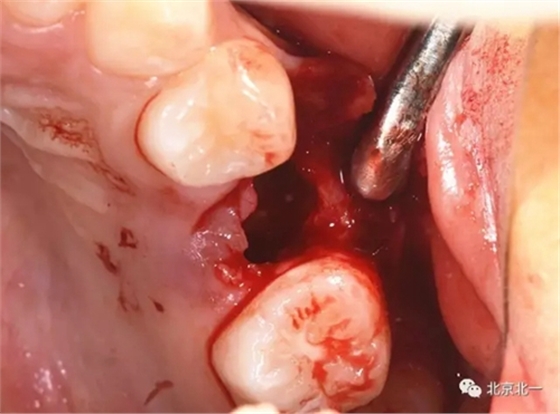

拔牙前臨床照片

術(shù)中有絲分裂